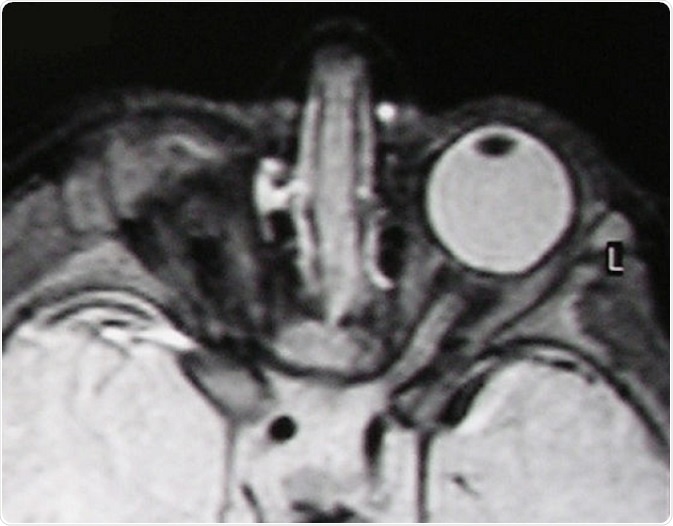

T2-weighted MR scan of a patient with unilateral anophthalmia. Note the presence of amorphous tissue and structures resembling extraocular muscles within the anophthalmic right orbit. The right optic nerve/chiasm junction appears attenuated rather than absent suggesting possible residual optic nerve neural tissue. © Verma AS / Wikimedia Commons.